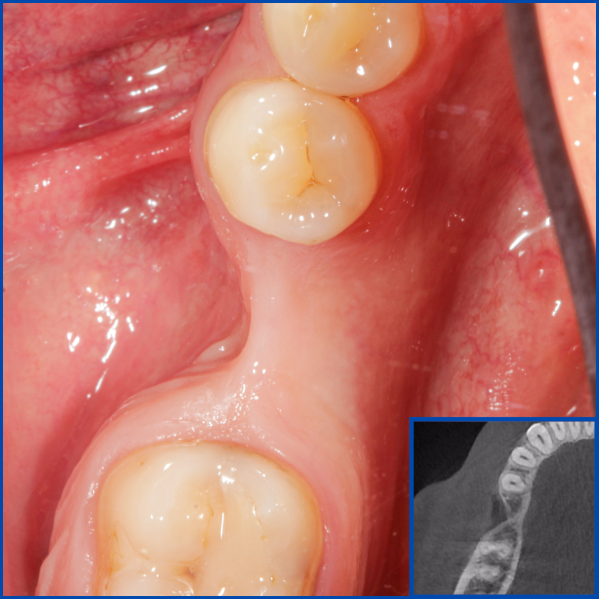

Kist nedeni ile çene kemiğinde defekt oluşmuş vakamıza sert ve yumuşak doku ogmentasyonu uyguladık.